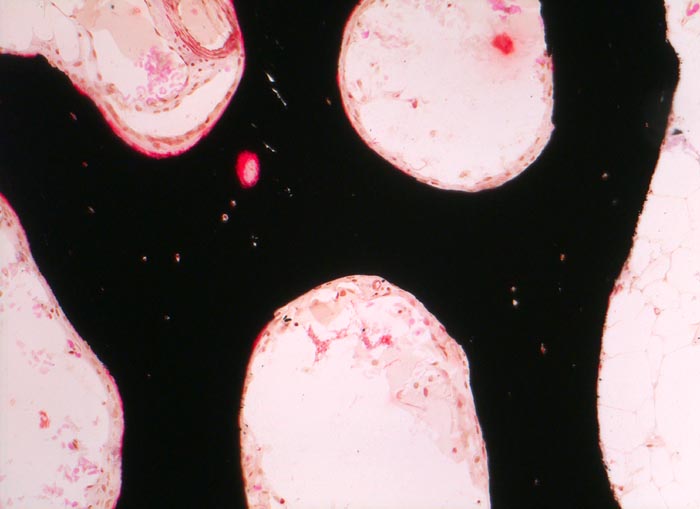

Durch eine Tetrazyklinmarkierung in zeitlich definiertem Abstand vor einer Knochenbiopsie kann die Mineralisationsdynamik abgeschätzt werden, da Tetrazykline bei der Mineralisation in den Knochen miteingebaut werden und im Fluoreszenzmikroskop identifiziert werden können.

Morphologische Merkmale (Goldner Färbung):

• Verbreiterte unmineralisierte Osteoidsäume (rot).

• Reduzierte Menge von mineralisiertem spongiösem und kortikalem Knochen (grün).